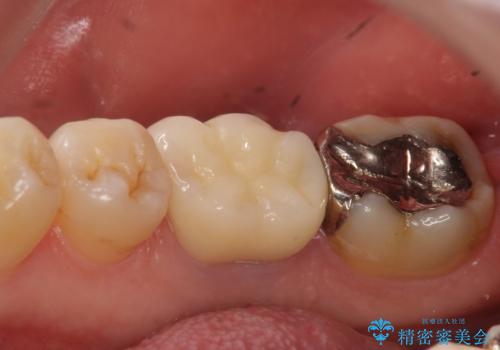

- 数年前から歯茎から膿が出る、治療してもよくならないので診て欲しいといらっしゃった方の症例です。

再根管治療を行い膿の出口の消失及び根尖病変の縮小を確認後、オールセラミッククラウンによる補綴を行いました。

今回用いたオールセラミッククラウンはジルコニアフレームという白い素材の上にセラミックを盛っているため、審美性が非常に高いのが特徴です。

また、ジルコニアは人工ダイヤモンドの材料にも使われているほど高い強度を持っており、そのためオールセラミッククラウンは審美性だけでなく、奥歯やブリッジの補綴も可能とするクラウンです。